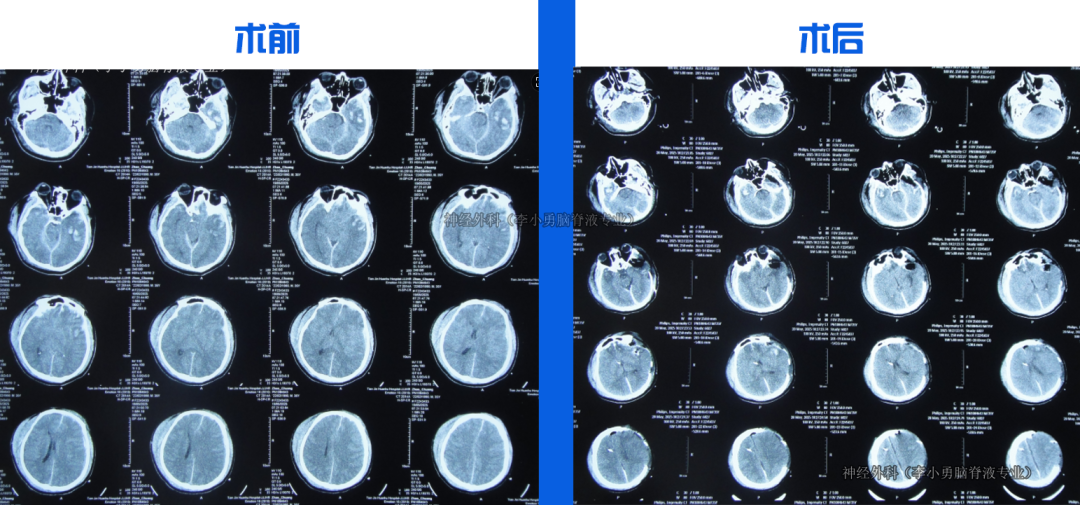

入院时:意识模糊,右上肢活动差,鼻饲、留置尿管。CT示颅骨缺损、脑积水、脑膨出。

入院当天行脑室外引流术。治疗18天后意识转清,脑脊液由浑浊变清亮。第22天改为脑室腹壁外引流,持续引流、抗感染、控制颅内压力。第36天骨窗开始塌陷,提示颅内压力有效控制。住院1月零23天行颅骨修补术。